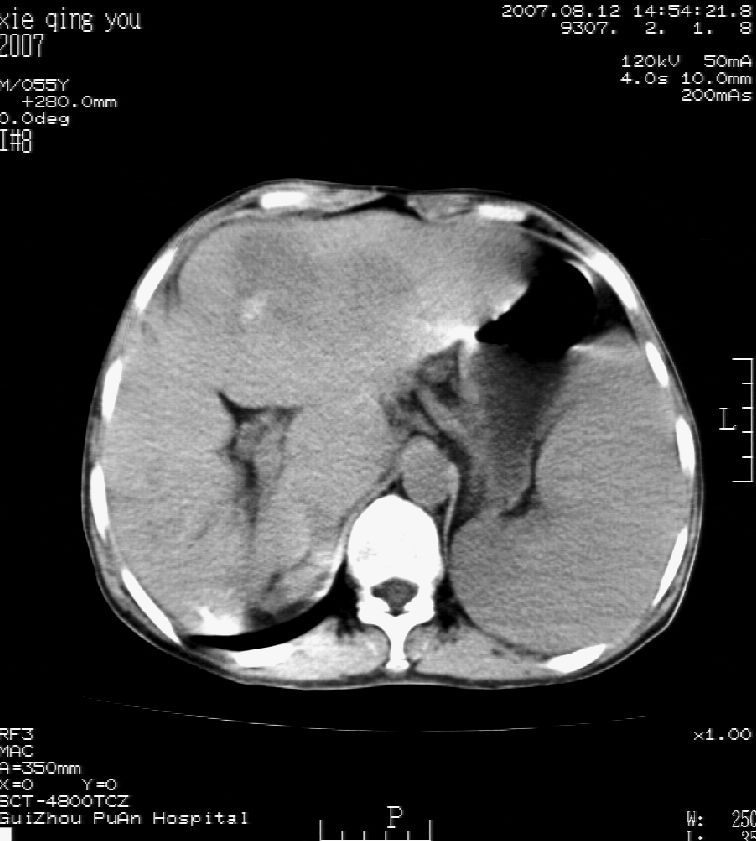

2007年8月片

这个病灶很有意思,怎么可能没有了呢?我考虑当时很可能是肝脏脓肿(b超示囊肿是有可能误诊的,因为影像表现都是低回声吗?),现在脓肿吸收了,肝脏萎缩,肝裂增宽了.别的肝叶代偿增大,不过现在左内叶的确有个占位,肝内多发结石,脾脏比以前大,不排除有肝硬化可能.建议增强扫描给于定性!!!!

肝硬化\\脾大,肝左叶肝癌可能性大,建议增强扫描.肝内胆管多发性结石.

1, 肝硬化,脾大;2,肝左叶肝癌可能性大,建议增强扫描.3,肝内胆管多发性结石.

至于肝右叶病灶为什么消失只有结合治疗史综合考虑。

考虑肝内胆管多发结石引起的肝内局部炎症,这样可以解释2005年肝右叶病灶的吸收和左叶新病灶.

肝硬化、脾大、肝内胆管多发结石。肝左叶低密度占位。建议增强扫描.排除肝癌